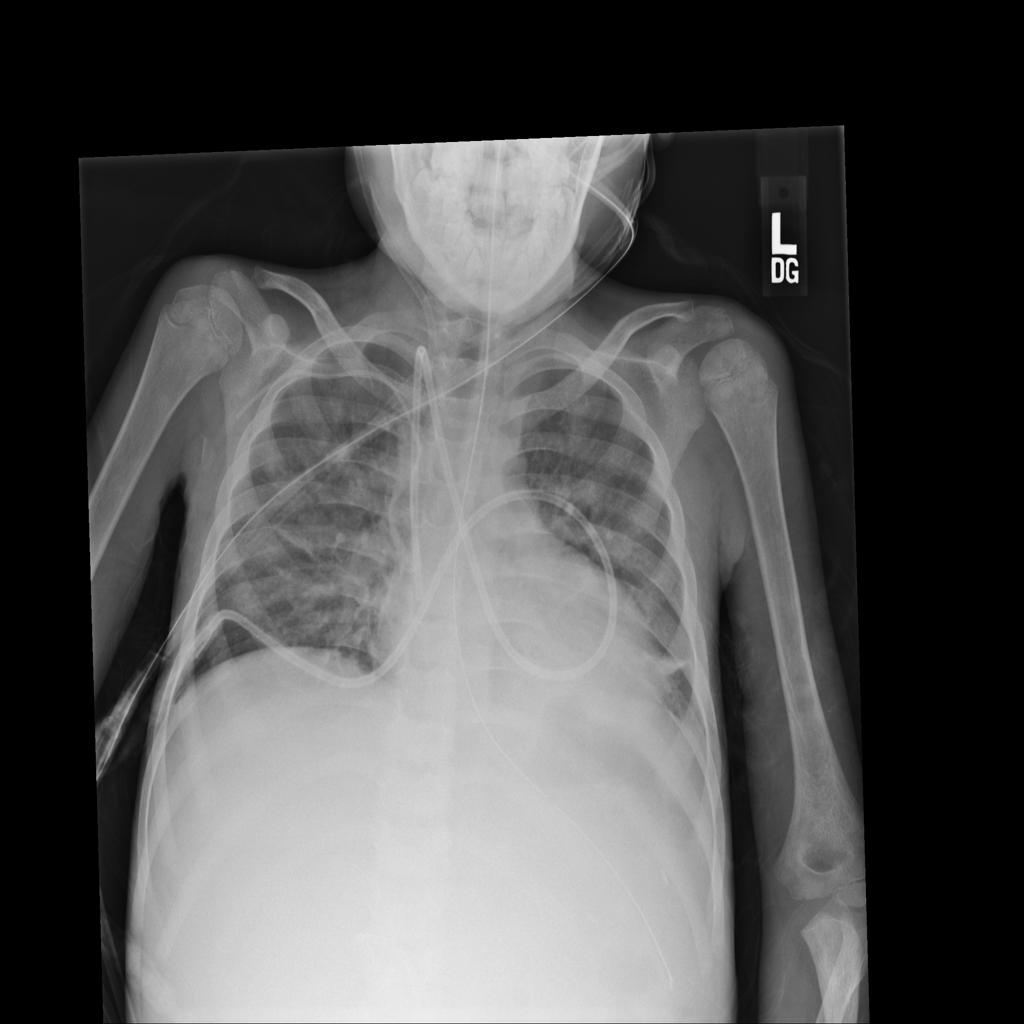

PAT-C1A7 · IMG-004Consolidation

PAT-C1A7 · IMG-004

PA